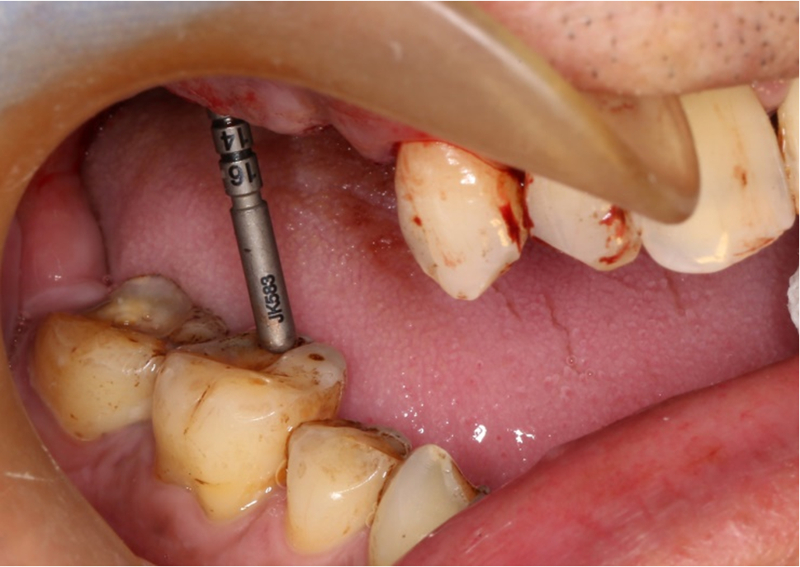

術中操作

®完成標定及配準

®按照術前方案進行備洞及植體植入

®按照術前方案進行備洞及植體植入,醫(yī)生可以通過屏幕軟件引導對手術中植入點、角度、深度實時追蹤

®對植體深度及方向進行確認

®完成3顆植體的植入,植體位點如術前方案設計,均在同軸線。